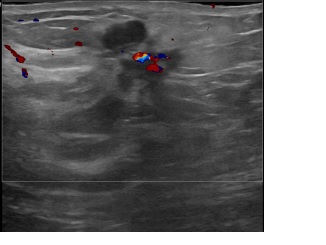

아산유외과개원후 828번째 유방암진단

상기환자는 좌측 만져지는 멍울로 내원하신 40대초반

여성분으로 의심스러운 좌측혹 조직검사 시행해 침윤성암으로 진단되었습니다